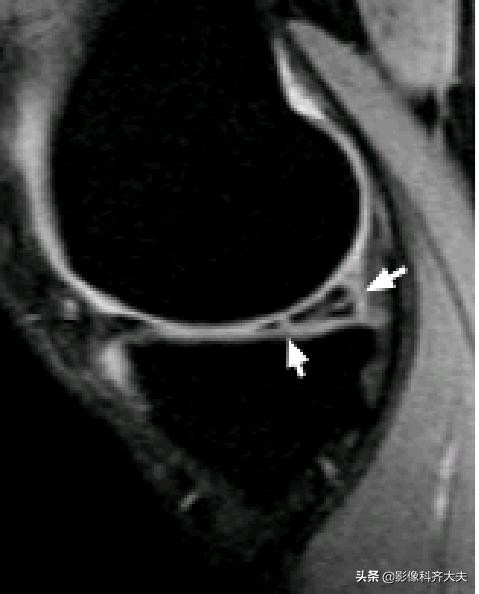

容易误诊为半月板损伤的正常解剖结构

膝横韧带:

腘肌腱腱鞘:

后股板韧带:

内侧半月板后角上隐窝: